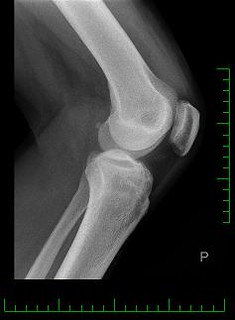

관절염

관절염은 관절에 염증을 일으키는 만성 질환입니다. 골관절염, 류마티스 관절염 및 통풍을 포함하여 무릎 관절에 영향을 줄 수 있는 여러 유형의 관절염이 있습니다. 관절염은 무릎 관절에 통증, 부기 및 뻣뻣함을 유발할 수 있습니다.